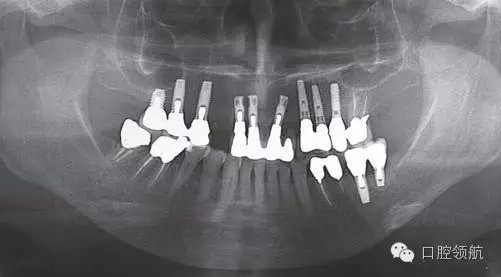

患者,66歲,女性。(左上第3顆牙)缺失的病例(圖1)(左上第4、5顆牙)部位已經(jīng)進(jìn)行了種植體修復(fù),從CBCT的影像診斷,(左上第4顆牙) 種植體頰側(cè)的骨吸收明顯,而且伴有周圍的軟組織的萎縮和種植體頸部的金屬暴露(圖2)。為了在(左上第三顆牙) 種植術(shù)后不再發(fā)生同樣的問(wèn)題,有必要進(jìn)行怎樣的處理呢?

圖1 (左上第3顆牙)缺失的全景X線片。